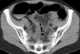

Trauma with colonic perforation

Gastrointestinal perforation, also known as ruptured bowel, is a hole in the wall of part of the gastrointestinal tract. The gastrointestinal tract includes the esophagus, stomach, small intestine, and large intestine. [Source: Wikipedia ]